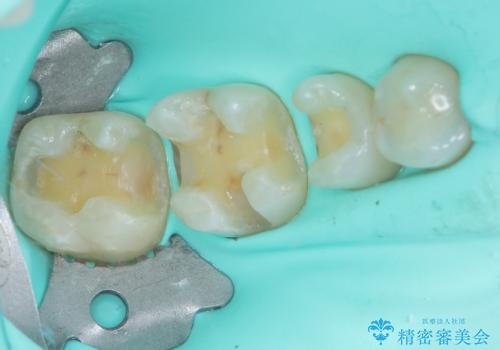

- 銀歯をセラミックにしたいとのことで来院された患者様です。

まず麻酔をして銀歯を外し、むし歯を除去し、形を整えて型取りします。

そして次の来院時、セラミックインレーを装着し、噛み合わせなどの調整を行います。

それを左右に分けて行いました。

インレーを装着するときは、唾液や血液による接着力の低下を避けるためにラバーダム防湿を行いました。